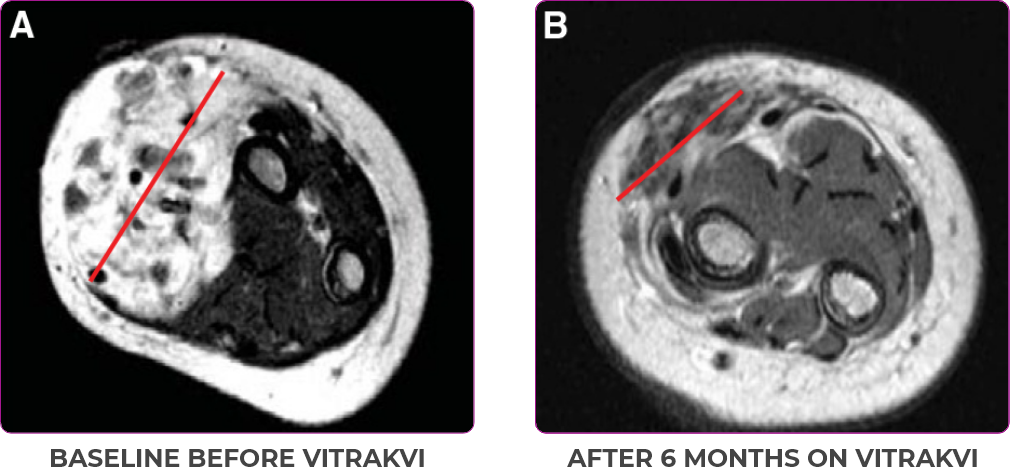

Reduction in tumor burden1

MRIa imagery of the brain. Red line indicates the maximum dimension.1

aMRI, magnetic resonance imaging.

Pre- and post-treatment imaging, by DuBois SG et al, is licensed under CC BY 4.0.

aIFS, infantile fibrosarcoma; MRI, magnetic resonance imaging; pCR, pathological complete response; PR, partial response.

Response to VITRAKVI1

- Patient achieved a confirmed partial response after 4 cycles of VITRAKVI with a 45% reduction in tumor burden

- Following 6 cycles of VITRAKVI, the patient was referred for definitive limb-sparing surgery

- Pathology revealed a complete pathologic response and clear resection margins with scar tissue noted